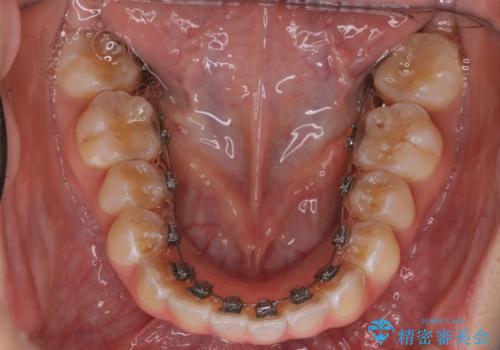

「フルリンガル矯正|アンカースクリューを活用し正中を整えた症例」

- 治療計画

矯正装置を装着し、アンカースクリューを活用しながら奥歯を少しずつ後ろへ動かし、正中を整えていきました。治療には時間がかかりましたが、計画通りに歯を移動させ、バランスの取れた歯並びへと仕上げることができました。裏側矯正のため、見た目を気にすることなく治療を進められた点も、患者様にとって大きなメリットでした。治療後は、「正中がしっかり合って、口元がスッキリした」とご満足いただきました。